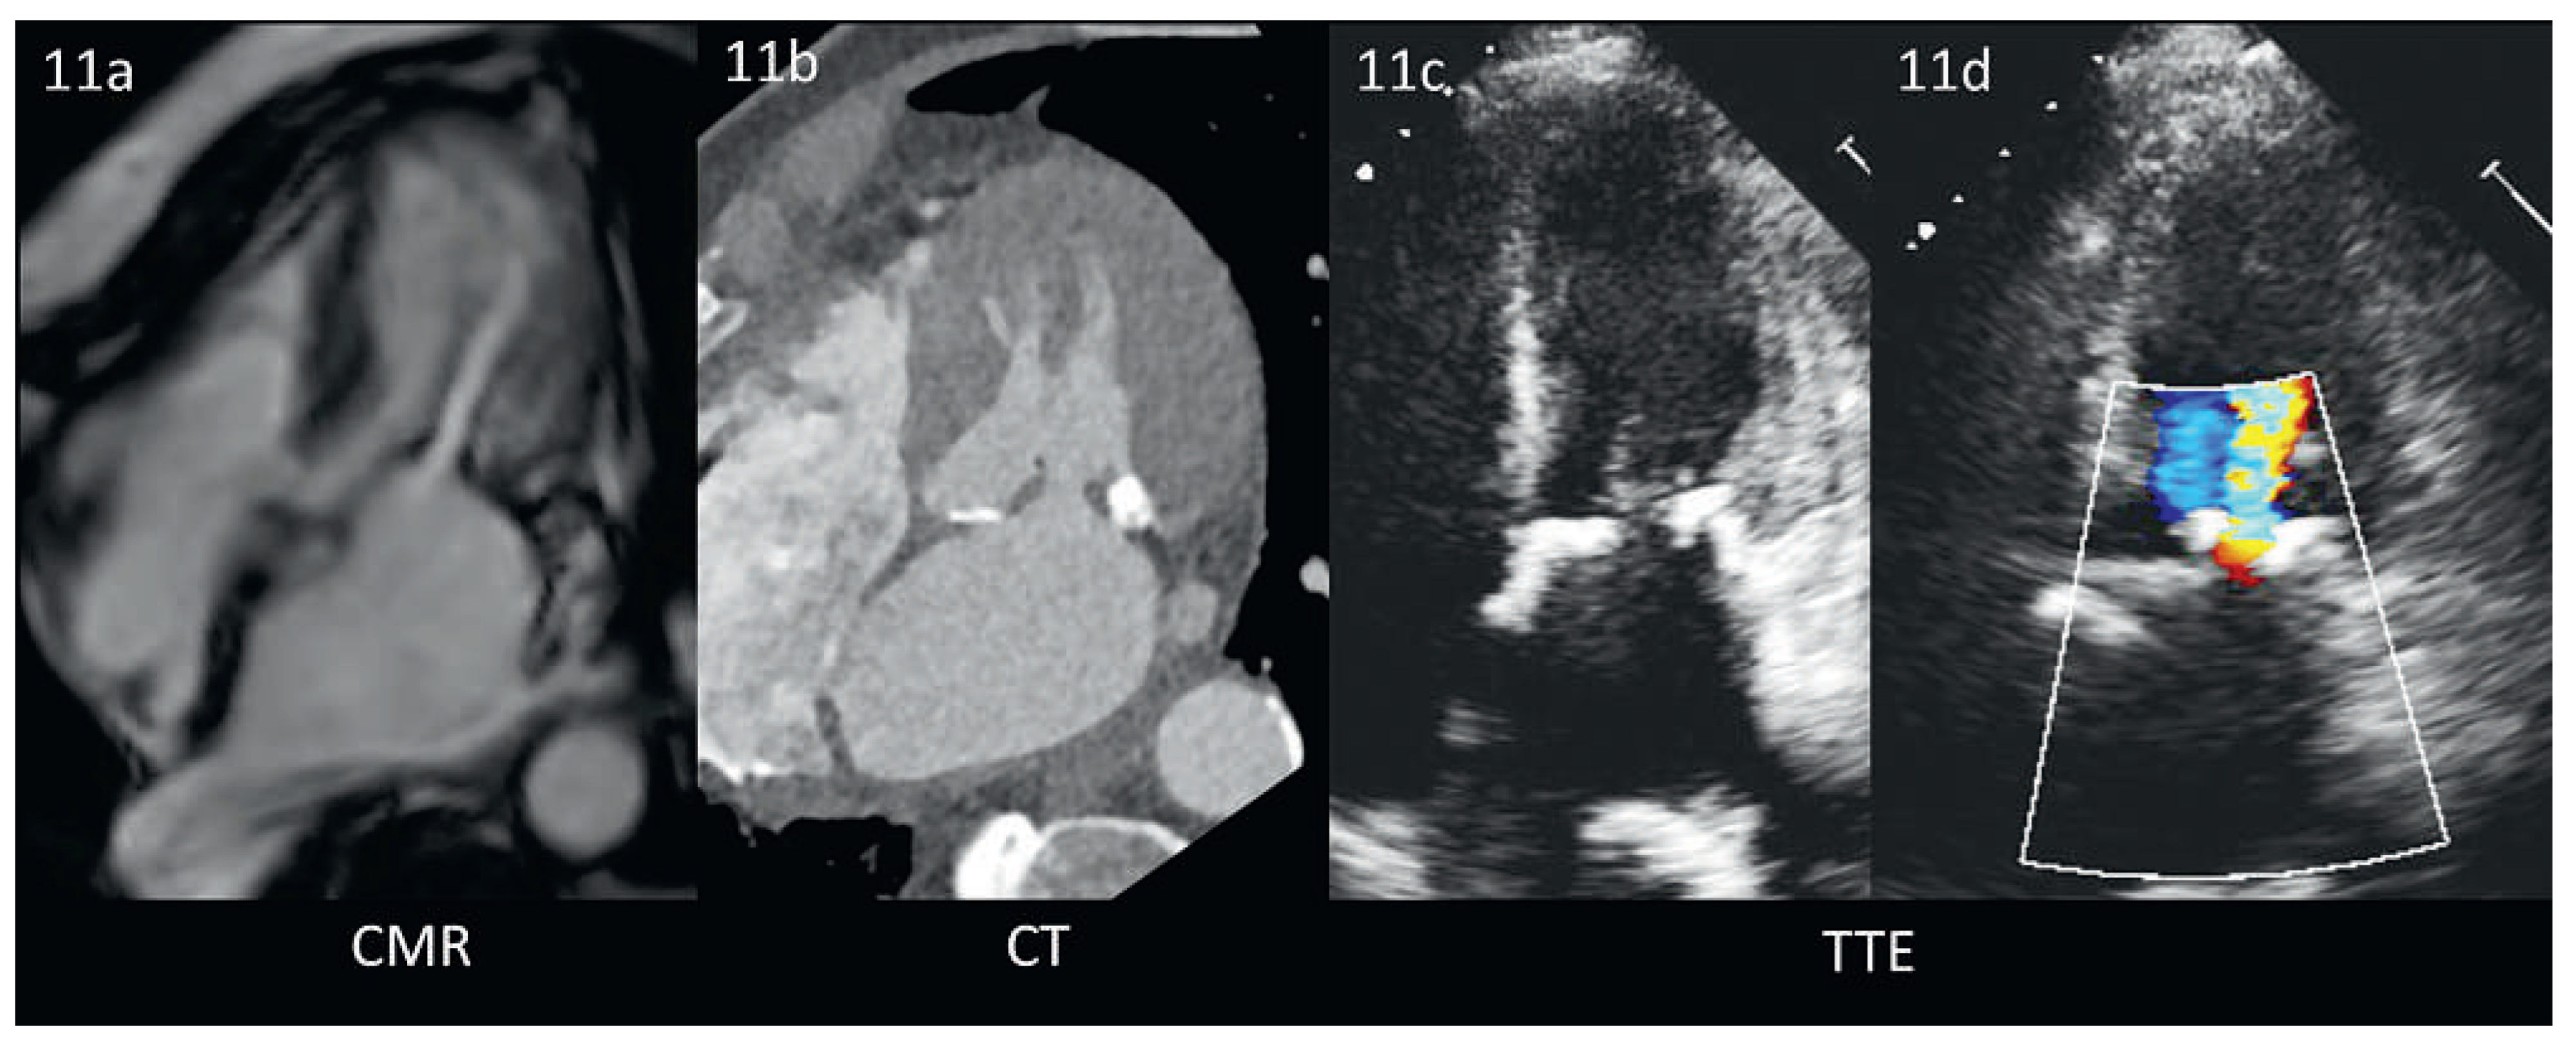

Abbildung 11. Mitralklappenstenose bei verkalkten Segeln im CMR, CT und TTE (identischer Patient). 11a: Die CMR ist zur Darstellung von Verkalkungen wenig geeignet, zeigt aber ähnlich wie die Farb-Doppler Echokardiographie (11d) die Flussbeschleunigung über der stenotischen Klappe gut. Abb. 11b: Im CT lassen sich die verkalkten Strukturen präzise vom umliegenden Gewebe abgrenzen. Abb. 11c/d: Diese Verkalkungen sind auch in der Echokardiographie gut darstellbar. Die gleiche Darstellung ist aber selbst beim identischen Patienten eine Herausforderung.